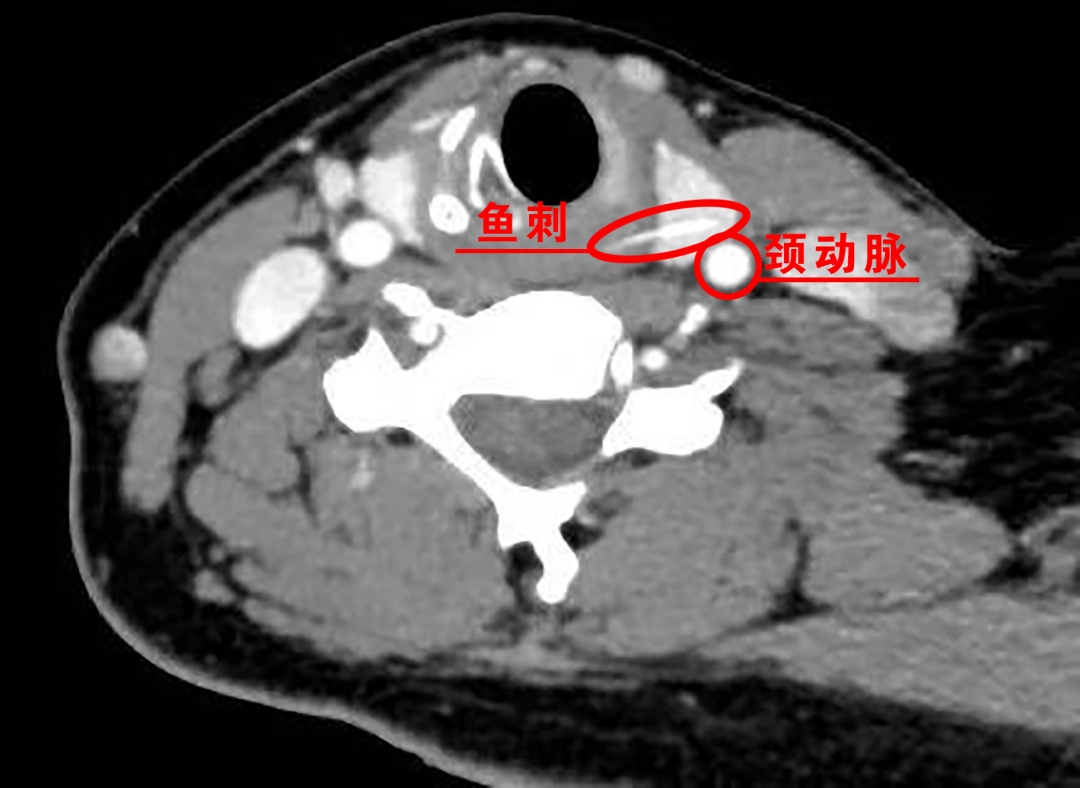

瑞金医院普外科主任医师、瑞金医院南翔分院院长吴庆华告诉记者,由于张女士鱼刺被卡时间较长,医院立即为她做了颈部增强CT检查,结果显示,食管入口偏左侧可见一条约1.7厘米的高密度条状影,已穿破食管扎进了甲状腺组织,鱼刺末端距离左侧甲状腺被膜(紧邻左侧颈总动脉)仅约3.4毫米!

鱼刺扎进甲状腺绝非小事

不仅会带入细菌引发

严重的深部脓肿甚至致命的纵隔感染

更因紧邻颈动脉等大血管

随时可能因移位

刺破血管导致瞬间大出血休克;